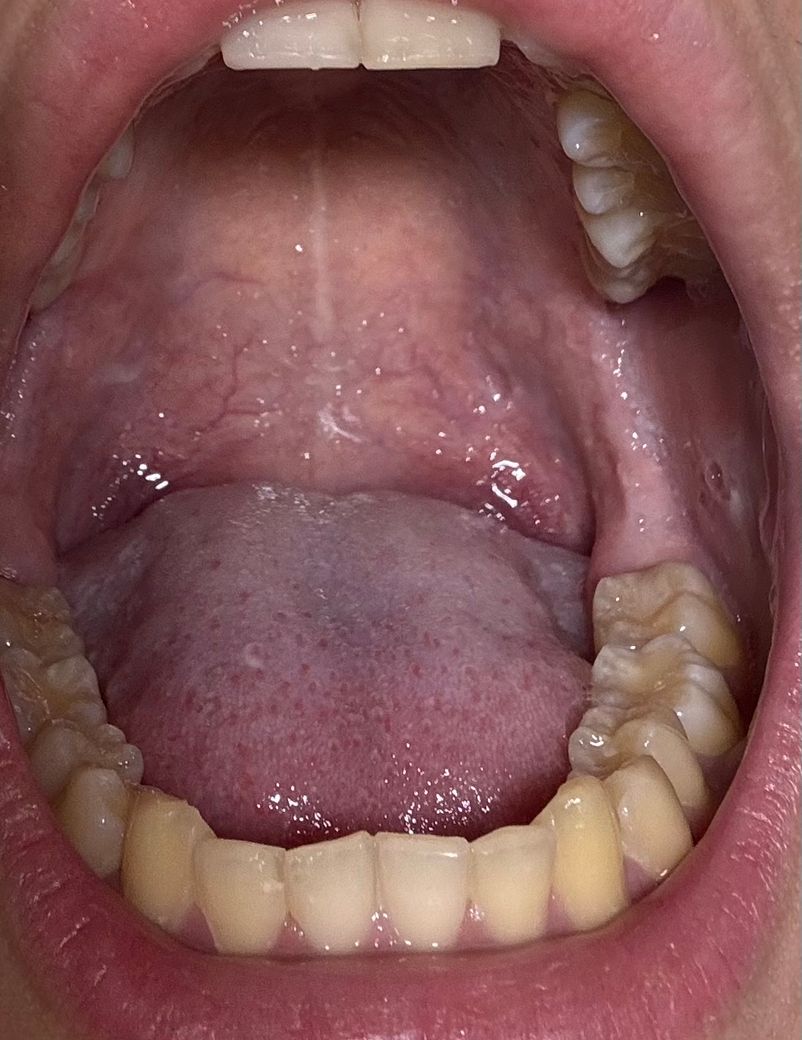

혹시 헤르페스 가능성이 있을까요??

구강성교 후 입에 정액을 받았는데 다음날 입 안쪽에 좁쌀 여드름같은게 올라오고(원래 있었는지는 모르겠어요ㅜ) 목이 부엇어요

혹시 헤르페스가능성이 있을까요?

(상대방한테 수포같은건 안보였어요)

위 사진만 봐서는 확인을 할 수는 없으며 수포가 커지거나 한다면 가능성이 있으니 검사받으러 가시면 됩니다.

헤르페스는 아닌거 같고 단순 수포 같습니다. 일단 컨디션 조절을 하시면 괜찮아 지실꺼에요.

구강성교 후 입 안쪽에 좁쌀 여드름 같은 이상증상발생 및 목 붓기가 생겼다면 헤르페스를 포함한 구강염증 가능성이 있습니다. 헤르페스일 가능성은 있지만 다른 감염이나 자극에 의한 염증일 가능성도 있습니다.

헤르페스 초기 증상은 입안에 물집, 작은 궤양, 따가움, 발적 등이 나타날 수 있습니다. 증상이 2~3일 내로 호전되지 않거나 악화되면 반드시 병원 방문하여 검사를 받아보길 권합니다.